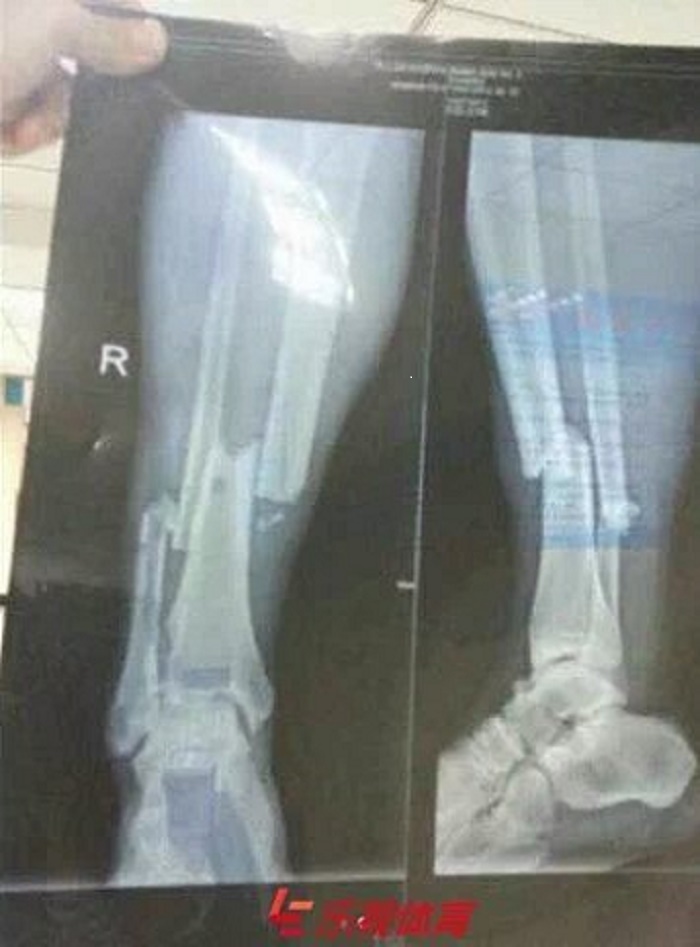

Title : Horrible La Radio De La Jambe Cassee De Demba Ba Source : www.football.fr Open New Window

Title : L Horrible Radio Du Tibia De Demba Ba Apres Sa Blessure Goal Com Source : www.goal.com Open New Window

Title : L Horrible Radio Du Tibia De Demba Ba Apres Sa Blessure Source : www.pressafrik.com Open New Window